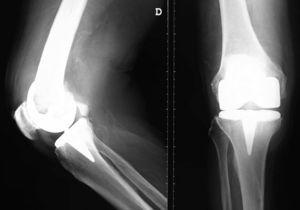

Acudió a Urgencias por presentar malestar general y fiebre de hasta 38,5°C, en ese momento se extrajeron hemocultivos y fue dado de alta con tratamiento oral con ciprofloxacino, tratamiento que no cumplió. Seis días después persistía la fiebre y en los hemocultivos (2/2) se identificó L. Monocytogenes tipo 1, por lo que se recomendó al paciente que acudiera de nuevo a Urgencias. Refería dolor, tumefacción y limitación funcional progresivos durante la semana previa en la rodilla derecha. En la exploración presentaba signos inflamatorios en la rodilla derecha junto con una tumoración fluctuante en el hueco poplíteo (figura 1). La temperatura era de 36,5°C. Entre las exploraciones complementarias destacaba una anemia (hemoglobina [Hb] de 9,2g/dl) normocítica y normocrómica y elevación de reactantes de fase aguda (proteína C reactiva de 77mg/l y fibrinógeno de 803mg/dl). A la vista de estos hallazgos se extrajeron nuevos hemocultivos y el paciente ingresó en la planta de hospitalización de Enfermedades Infecciosas; se inició un tratamiento parenteral con ampicilina y gentamicina. A las 24h se realizó un ecocardiograma transesofágico en el que no se apreciaron signos de endocarditis. Asimismo, se realizó artrocentesis de la rodilla derecha y se obtuvo un líquido articular en el que destacaba la presencia de leucocitosis (11,9 × 109/l) con predominio de polimorfonucleares (80,5%) y glucosa normal. En el líquido creció L. monocytogenes tipo 1 polisensible. Los hemocultivos extraídos al ingreso, antes de iniciar el tratamiento antibiótico, también resultaron positivos para el mismo microorganismo.

Figura 1. Tumoración fluctuante en hueco poplíteo derecho.